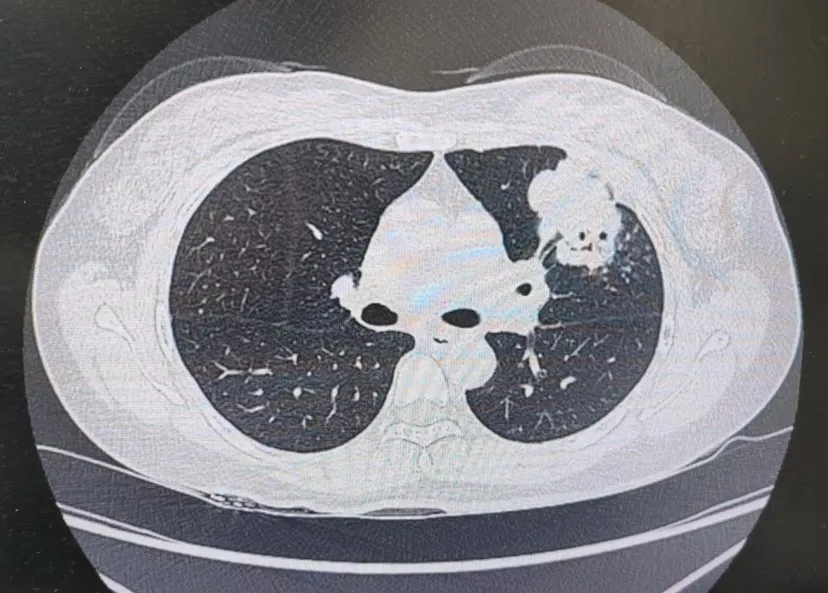

患者肺部CT影像

“一般來說,肺炎經(jīng)過一周的抗感染治療,病灶會有所吸收。但陳女士的肺部陰影紋絲不動,這種情況必須提高警惕。”宋剛主任團隊立即啟動了更深入的“三部精準診斷”程序:

3、CT引導(dǎo)下穿刺活檢:病理診斷為左肺上葉腺癌。

肺炎型肺癌,因其影像學(xué)表現(xiàn)與普通肺炎極為相似,臨床上誤診率極高。然而確診僅是第一步。宋剛主任當天即召集腫瘤科、病理科、影像科等多學(xué)科專家會診,為陳女士制定個體化治療方案。